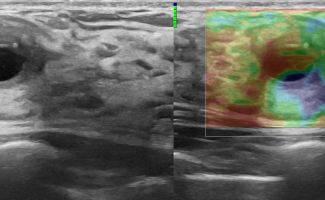

Elastography: The Additional Advantage in Breast Ultrasound

Modern ultrasound machines, equipped with advanced high-frequency transducers, techniques such as Color Doppler, Power Doppler, B-Flow, and Elastography, allow the analysis of breast architecture with exceptional accuracy.

Elastography can highlight the elasticity of a lesion, indicating whether it is hard or soft. Through this technique, we can assess the nature of the lesion, providing indications of whether it is benign or malignant. Additionally, with the contribution of Color Power Doppler and B-Flow, we can monitor the vascular flow within the lesions, offering even more information about the type and nature of the abnormality.